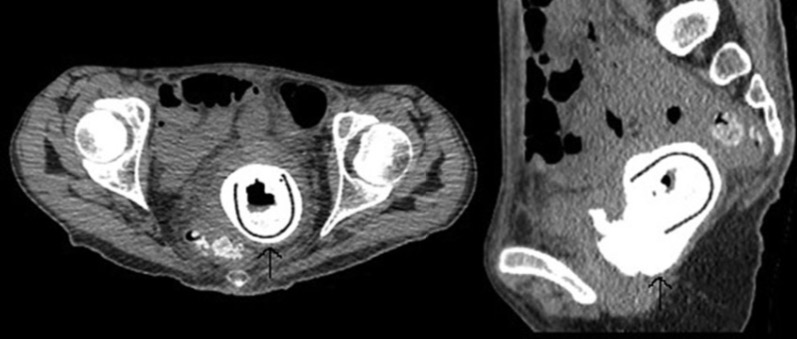

Figure 1. Неконтрастная компьютерная томография, демонстрирующая инородное тело во влагалище (стрелка).